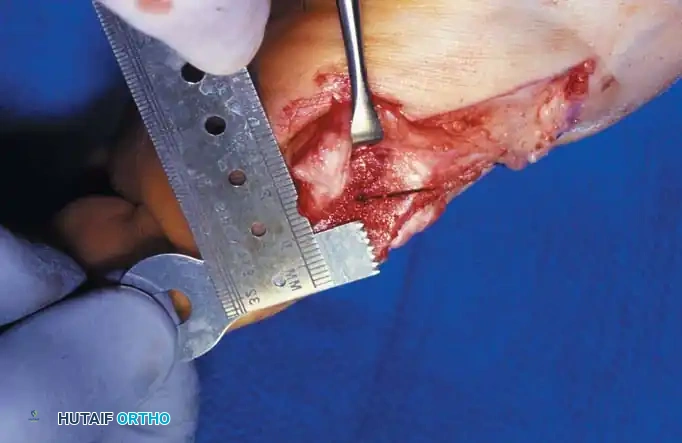

A B

Fig. 78-8 A, Determination of position of articular surface of metatarsal head in relation to longitudinal axis of fi rst metatarsal. B, Measurement of distal metatarsal articular angle at time of surgery. Markings are at medial and lateral margins of articular surface of fi rst metatarsal head and longitudinal axis of fi rst metatarsal shaft. metatarseum between the bases of the fi rst and second metatarsals might preclude the effectiveness of a soft-tissue procedure alone to provide suffi cient correction of the increased intermetatarsal angle. Likewise, accessory sesamoids and prominent ungual tuberosities at the interphalangeal joint contribute to a painful callus at the tibial side of this joint. An os tibialis externum frequently is associated with excessive hallux valgus interphalangeus. Varus of the fi rst metatarsal might be a signifi cant part of the overall deformity of the foot even with an intermetatarsal angle of less than 10 degrees. Metatarsus varus with a relatively small hallux valgus angle (15 to 20 degrees) may produce signifi cant deformity even though the angles are not excessive. The usefulness of computer-assisted compared with manual measurement of the intermetatarsal angle, hallux valgus angle, and distal metatarsal articular angle is still uncertain. Both methods have closer interobserver and intraobserver correlation in measurement of the intermetatarsal angle and hallux valgus angle than in measurement of the distal metatarsal articular angle. The reliability of either method has such a wide range (5 degrees), however, that measurements of these angles, although useful as a guide, do not provide a completely reliable indication of the magnitude of deformity. Condon et al. suggested that the reliability of the intermetatarsal angle can be improved by careful technique and by making the measurements at least twice and averaging them. Schneider et al. reported two methods of determining angular measurements based on distinctly different reference points: (1) a longitudinal axis of the fi rst metatarsal using middiaphyseal reference points, and (2) a center-head technique using a center head (center of the articular surface) and center base

(center of the proximal diaphysis) as reference points. They found that measured correction of the hallux valgus and intermetatarsal angles varied by approximately 9 degrees depending on which reference points were used. Recommendations of Coughlin, Saltzman, and Nunley (American Orthopaedic Foot and Ankle Society Ad Hoc Committee on Angular Measurements) included standardized radiographic technique, specifi c placement of reference points (Fig. 78-11), use of a protractor rather than a goniometer for measurements, and, after distal osteotomies, dual measurements using a center-head technique and a Mose sphere.